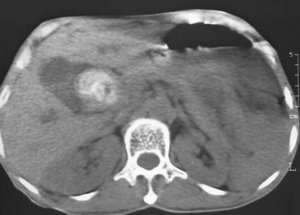

以下是引用lkc8963在2006-1-19 21:13:00的发言:[br]右半结肠及盆腔小肠明显积液扩张,腹腔内无明显渗出;右半结肠近端见多发点状高密度影;胆管内多发结石。[br]不知临床有哪些资料。本例需考虑胆石性肠梗阻的可能性,或胆系结石漏至结肠(异常通道如瘘)。

以下是引用wawaquan在2006-1-19 23:55:00的发言:[br]胆系结石,右半结肠梗阻:考虑横结肠占位(横结肠壁厚呈肿块状)。